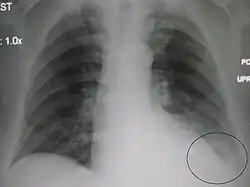

| A chest X-ray showing a very prominent wedge-shape bacterial pneumonia in the right lung | |

Right upper lobe pneumonia as marked by the circle. -